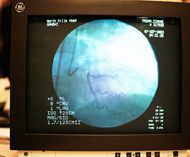

La venografía consiste en una exploración diagnóstica invasiva que permite el estudio de la circulación venosa de las extremidades inferiores. Las venas no son visibles en las radiografías simples. Para poder visualizarlas mediante un estudio de rayos X es necesario la inyección de un contraste venoso. El contraste es una sustancia radiopaca que no permite el paso de los rayos X a través de su superficie, por lo que permite visualizar aquellas venas que lo contienen. Durante la práctica de la prueba pueden tomarse varias radiografías para visualizar el llenado progresivo de los vasos y detectar estrechamientos, obstrucciones o la presencia de vasos anómalos.

Se realiza en salas o unidades de radiología. El paciente debe tener las piernas desnudas, evitando sobre todo la presencia de objetos metálicos que pudieran alterar las imágenes. Las extremidades se sujetan a una mesa de rayos X. La mesa puede inclinarse en varias posiciones. Se procede a canalizar una de las venas superficiales de la extremidad inferior a estudiar, generalmente en el dorso del pie, y se inyectará el contraste. Se le puede aplicar un anestésico local para adormecer el área donde se insertará el catéter, puesto que en ocasiones puede precisar de una pequeña incisión para facilitar la introducción del catéter. El personal de enfermería controla las constantes vitales y comprueba los pulsos dorsal del pie, poplíteo y femoral. Se indica al paciente que no mueva la pierna mientras se toman las radiografías.